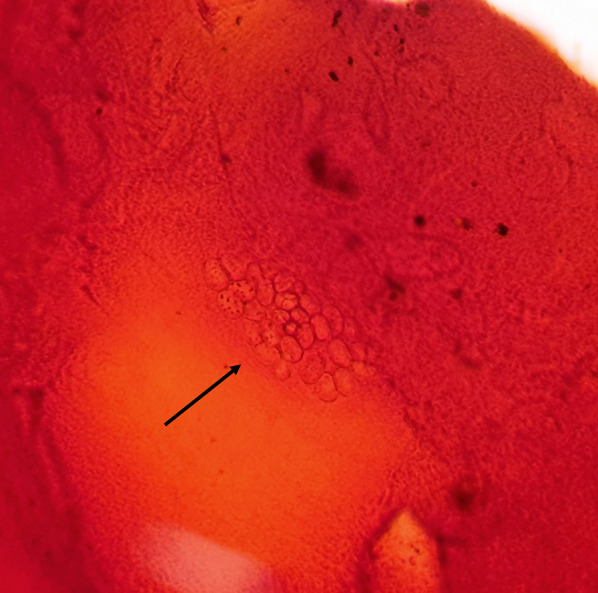

Fig. 4.

Microsporidial spores are seen as clusters of unstained halos in gram stain of the corneal scraping (black arrow)

(Photo from Dr. Jyoti Prakash Panda. Gram’s, × 100)